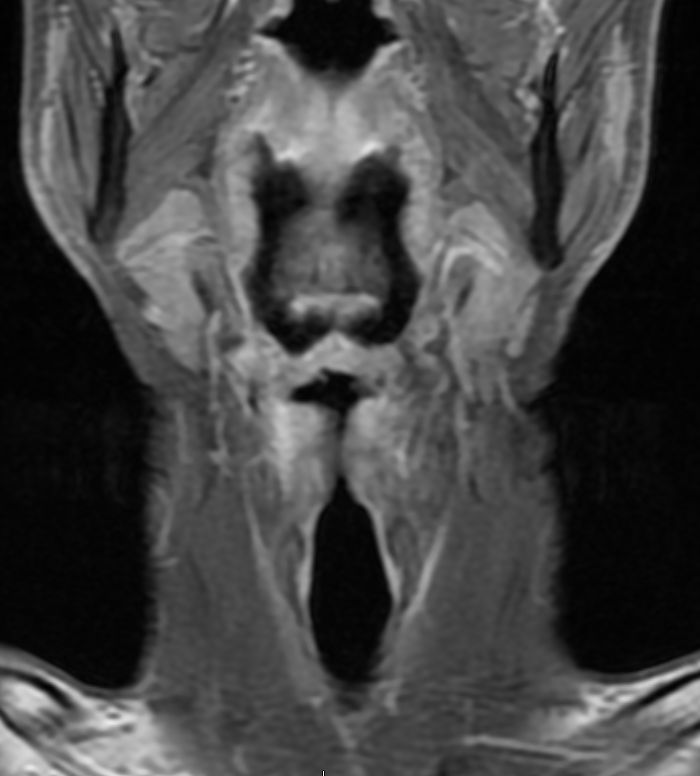

MRT: supraglottisch T3 No |

57-jähriger Mann mit langjährigem Alkohol- und Nikotinabusus. Seit 6 Monaten Schluckbeschwerden. Jetzt zunehmende Kachexie. MRT: Ausgedehntes supraglottisches Larynxkarzinom mit Schildkrorpel-Infiltration. Kehlkopfteilresektion mit ND. Histologie: unverhornendes Plattenepithelkarzinom, V0 R1 G1 - 2 Stadium post OP: pT3 pN0 (0/7) M0 | ||